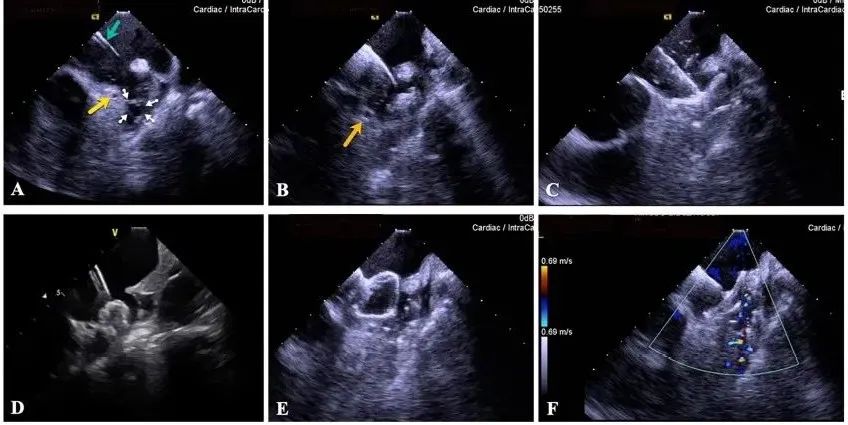

一種與心導(dǎo)管檢查相結(jié)合的超聲心動(dòng)圖診斷新興技術(shù),通過將超聲探頭置于心腔內(nèi)部,發(fā)射并接收超聲信號(hào),來精確獲取心臟解剖結(jié)構(gòu)、心臟血流動(dòng)力學(xué)等信息的實(shí)時(shí)成像。與其他影像技術(shù)相比,ICE技術(shù)具有操作簡單、無輻射、安全性高、手術(shù)效率高、實(shí)用等優(yōu)勢(shì),ICE在很大程度上有望取代經(jīng)食道超聲心動(dòng)圖(TEE),成為電生理和結(jié)構(gòu)性心臟病領(lǐng)域的理想成像方式。

目前ICE技術(shù)已被應(yīng)用于左心耳封堵、房顫射頻消融、二尖瓣成形、房間隔缺損封堵等多種心臟介入手術(shù),應(yīng)用場(chǎng)景主要圍繞心臟電生理、結(jié)構(gòu)性心臟病等領(lǐng)域,目前以電生理應(yīng)用為主。數(shù)據(jù)顯示,我國結(jié)構(gòu)性心臟病介入器械市場(chǎng)規(guī)模已從2017年的4億元增長至2021年的20億元,年復(fù)合增長率達(dá)48.3%;預(yù)計(jì)到2025年,該市場(chǎng)規(guī)模將達(dá)到104億元,可以預(yù)見ICE市場(chǎng)規(guī)模也將同步高速增長,未來市場(chǎng)發(fā)展空間廣闊。

心腔內(nèi)超聲(ICE)技術(shù)壁壘極高,國內(nèi)主要廠商核心部件仍舊為進(jìn)口,集成了超聲和圖像處理最前端技術(shù),包括超聲探頭、線纜、軟件成像算法等,是當(dāng)前內(nèi)窺超聲方向最具挑戰(zhàn)的領(lǐng)域。ICE的應(yīng)用經(jīng)歷了2D平面成像、3D三維立體成像、以及4D的實(shí)時(shí)三維立體成像階段。